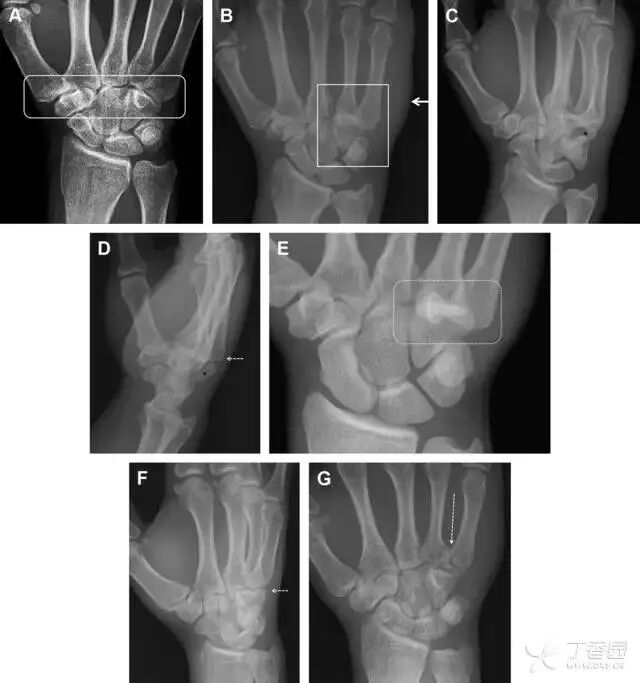

32掌板骨折

掌板是掌指关节和指间关节关节囊掌侧的纤维结构,防止关节过伸。掌板的远端部是增厚的纤维软骨,附着于指骨掌侧基底部,而其两侧与侧副韧带的纤维融合。掌板骨折多发生于过伸损伤,为撕脱性骨折。

图 3 掌板骨折(A~C)小指前后位、斜位、侧位片,由于骨折的部位及特点,在前后位片上通常难以发现骨折;放大后的斜位(D)、侧位(E)可见一骨碎片(白色箭头)

33腕掌关节骨折脱位

腕掌关节骨折脱位为高能量损伤,常伴有神经损伤。腕掌关节组成骨多,侧位片上重叠遮挡多,骨折不易发现,容易漏诊。在前后位片上,关节面不平滑、关节间隙不对称、关节皮质破坏、关节面重叠常提示腕掌关节骨折脱位。特别是第 4、5 腕掌关节脱位,在前后位片上不容易发现;该损伤不稳定,也称为「变异型拳击手损伤/骨折」。

图 4 第 4、5 腕掌关节骨折脱位。(A)正常腕掌关节,关节面平衡起伏、平行;前后位(B)、斜位(C)、侧位(D),第 5 掌骨近端附近软组织肿胀(白色箭头),冠状面关节面重叠,背侧撞击剪切应力致钩状骨骨折(*),在前后位及斜位片上可见双密度影。第 4 掌骨底部可见微小骨折碎片(D,虚线箭头),第 4、5 掌骨掌侧成角。(E~G)变异型拳击手损伤:第 4、5 掌骨背侧脱位而未见骨折(E,虚线方框),钩状骨有骨折小碎片(F,短虚线箭头),第 4 掌骨基底部关节内骨折(G,长虚线箭头)

34钩状骨骨折

钩状骨骨折可发生于体部和钩部,钩部骨折更多见,可合并有第 4、5 腕掌关节脱位。受伤机制由直接暴力或腕横韧带撕脱伤所致。骨折征象包括钩部无显示、骨皮质边缘模糊、硬化或双密度影等。常规的正侧位常无法明确诊断,需要加拍腕管位,可清晰显示其钩部。

图 5 打高尔夫球后腕部急性疼痛。常规腕关节 X 线片正常(X)。腕管位片(B)隐约可见钩部横行骨折(虚线箭头),CT 检查(C、D)进一步明确了诊断